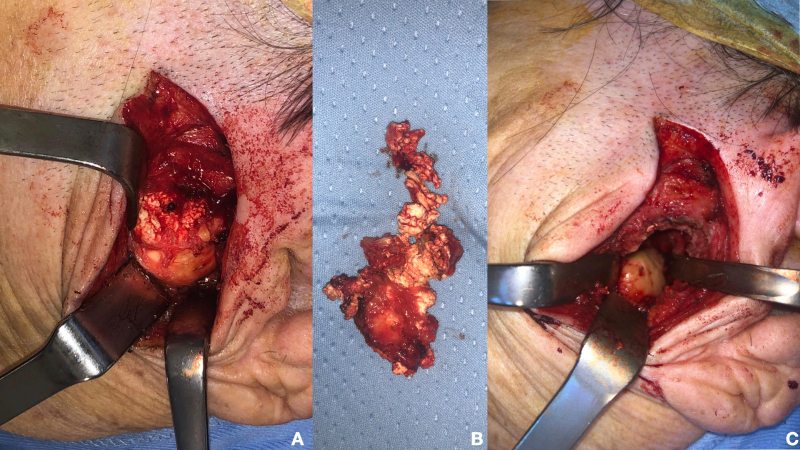

Conclusions: CPPD is an uncommon, locally invasive, and typically benign condition that rarely affects the TMJ. Distinguishing CPDD in the TMJ from other neoplasms poses diagnostic challenges. A definitive diagnosis necessitates histological examination and quantitative microanalysis. In our patient, successful excision of CPDD in the TMJ was achieved using an external approach.